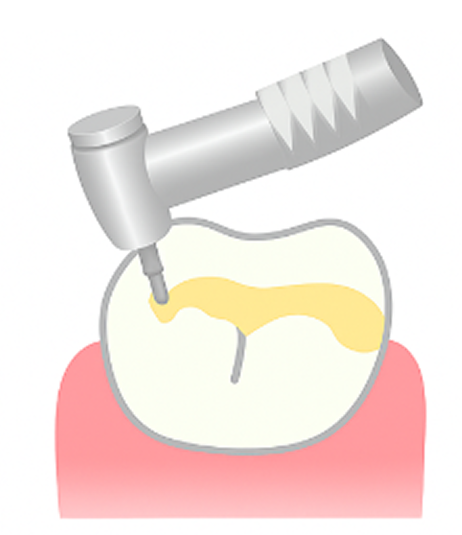

エナメル質がに虫歯が進行した初期の虫歯です。痛みなどの自覚症状はほとんどなく、 この段階ではプラスチックの樹脂を使ったCR(コンポジットレジン)修復を行います。

CRを使う場合もありますが、進行していれば型取りをして詰め物や被せ物を行います。